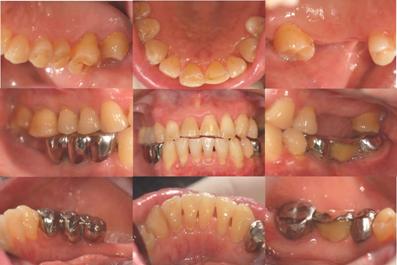

患者,女,63岁。十余年来刷牙出血明显,伴上后牙松动及咀嚼无力症状。半年前更换降压药,服用“非洛地平片”(1片/天)及“新达苏”(1片/天)后,上述症状加重。四月前加服“倍他乐克”及“络活喜”(1片/天)后,病情继续进展,并于2月前出现右下前牙牙龈肿胀伴松动症状。

• 口腔卫生状况:差,大量菌斑、软垢,龈下牙石(+++)

• 牙龈炎症: 43-41唇侧附着龈波及牙间乳头可见15×10mm深红色椭圆形肿胀,BI4;其它上下前牙及后牙区可见程度相对较轻牙间乳头肿胀,质软,BI3-4

• 探诊检查:42颊侧中央PD8mm,余位点5-7mm ;25远中PD10mm,松III°,AL>10mm ; 余后牙邻面PD5-8mm,AL>5mm,FI1-2;上前牙PD4-8mm,AL3-4mm

治疗前口内相